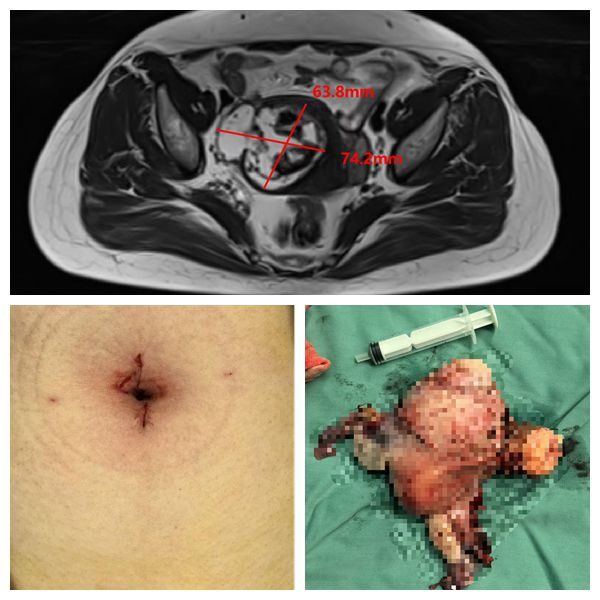

患者张女士,体检发现子宫肌瘤伴增大1年之主诉入院,MRI检查提示子宫肌瘤伴变性,肿瘤大小约74mm×63mm×58mm。根据诊疗指南建议行全子宫双附件切除术。王国庆主任医师团队认真评估患者病情,经过充分的术前准备、手术规划,在全麻下顺利完成了“达芬奇”机器人单孔腹腔镜下全子宫双附件切除术。手术时,王国庆主任医师在患者肚脐开一个3厘米切口,手术历时2小时分钟,术中几乎“零出血”,术后伤口美观,患者快速恢复。

(整个子宫包含直径达7cm的子宫肌瘤和双附件被成功取出)